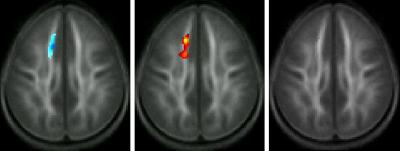

Keller and Just's study was designed to discover what physically changes in the brains of poor readers who make the transition to good reading. They scanned the brains of 72 children before and after they went through a six-month remedial instruction program. Using diffusion tensor imaging (DTI), a new brain imaging technique that tracks water movement in order to reveal the microscopic structure of white matter, Keller and Just found a brain change involving the white matter cabling that wires different parts of the brain together.

Previous DTI studies had shown that both children and adults with reading difficulty displayed areas of compromised white matter. This new study shows that 100 hours of intensive reading instruction improved children's reading skills and also increased the quality of the compromised white matter to normal levels. More precisely, the DTI imaging illustrated that the consistency of water diffusion had increased in this region, indicating an improvement in the integrity of the white matter tracts.

"The improved integrity essentially increases communication bandwidth between the two brain areas that the white matter connects, by a factor of 10," Just said. "This opens a new era of being able to see the brain wiring change when an effective instructional treatment is applied. It lets us see educational interventions from a new perspective."